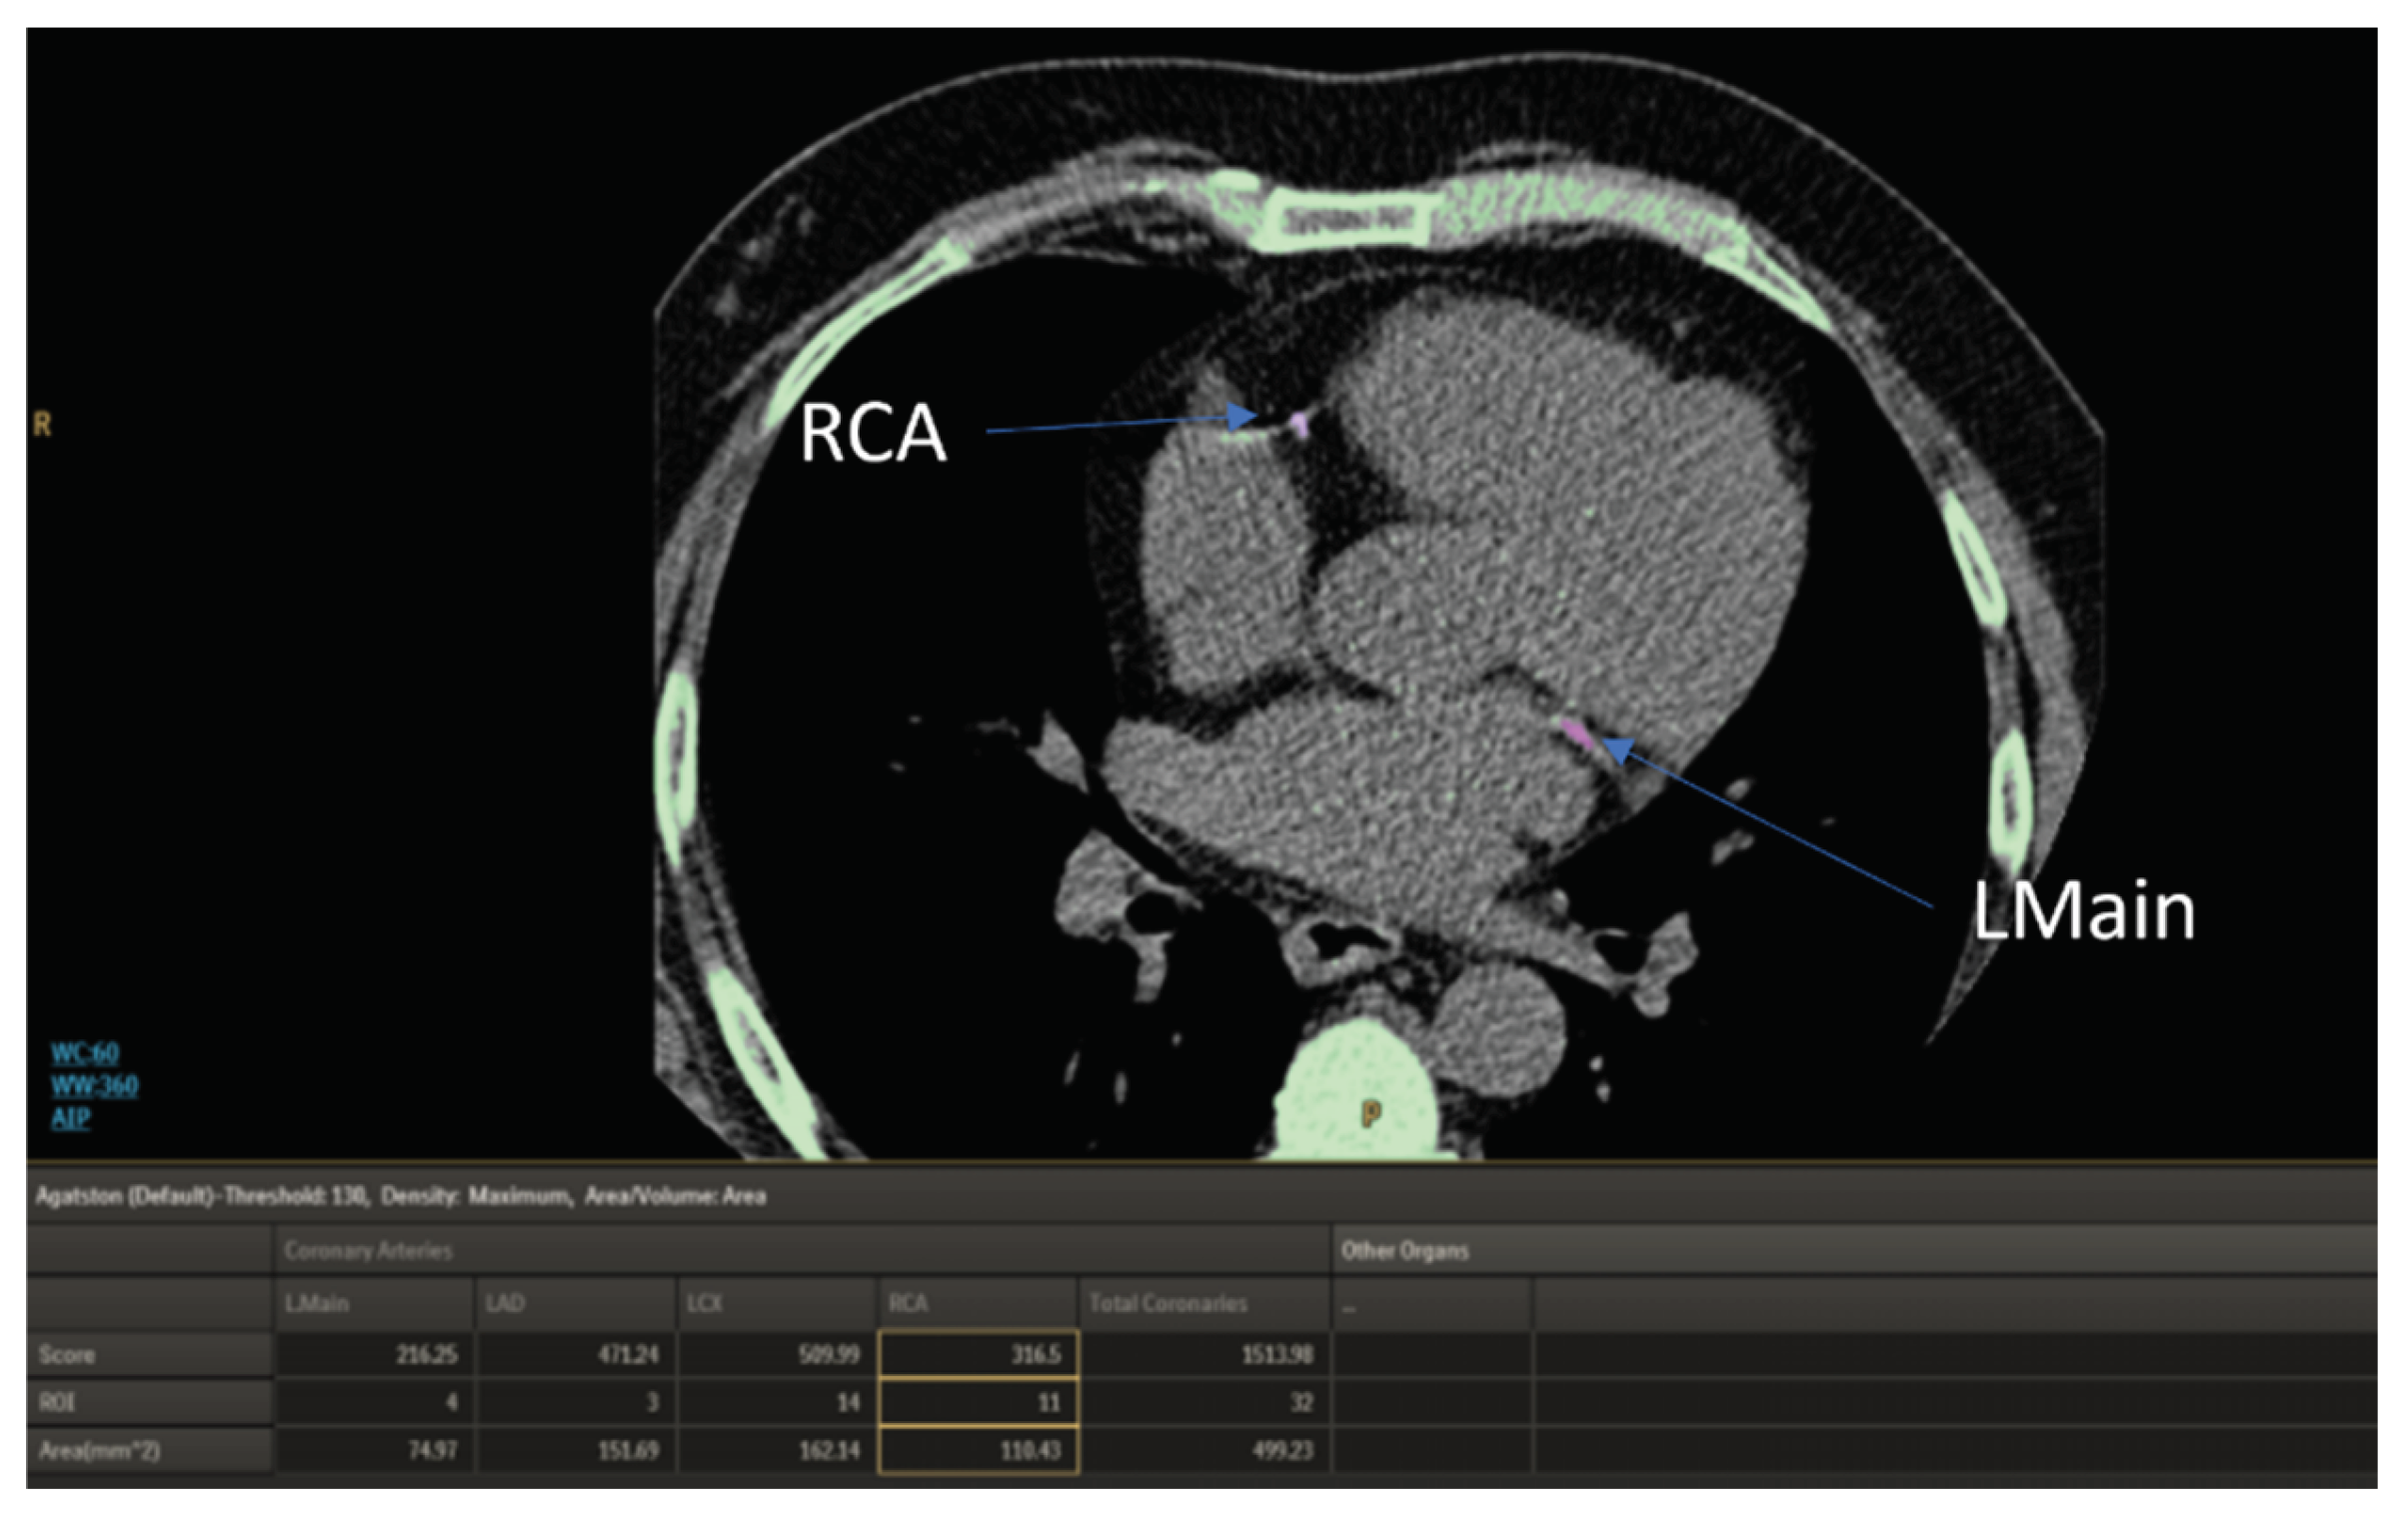

3.2.3. Non Contrast Enhanced Computed Chest Tomography, NCECCT

| Scoring | Interpretation |

| 0 | no measurable calcified plaque |

| 1-10 | Minimal |

| 11-100 | Mild |

| 100-400 | Moderate |

| > 400 | Extensive |